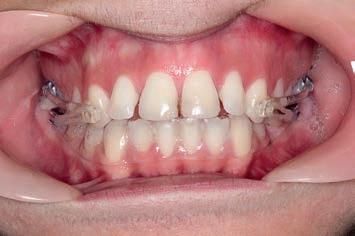

The first wire, a .014 round Cu Nitanium wire, corrected the rotations of the incisors. With the .014 x .025 Cu Nitanium wire, power chain was used to close the spaces between the incisors. After these spaces closed, the .017 x .025 Cu Nitanium wire would begin torque control with the final archwire, the .019 x .025 Cu Nitanium wire, to finalise the axial angulations of the anteriors. When the upper .019 x .025 archwire was engaged, three links of power chain were run bilaterally from the 2nd premolar to the 1st premolar and from the 1st premolar to a crimpable hook attached to the wire distal to the lateral incisor to retract the anterior segment, bringing it into the final desired position.

11 months: Sagittal and fixed appliance treatment complete

With 3 months of sagittal treatment and 8 months of fixed appliance treatment, the case finished to a harmonic occlusal and facial result. The result exhibits an excellent repositioning of the mandible held in position by the occlusal lock of the Class I platform (intercuspation of the molars, premolars and canines). The mandibular repositioning